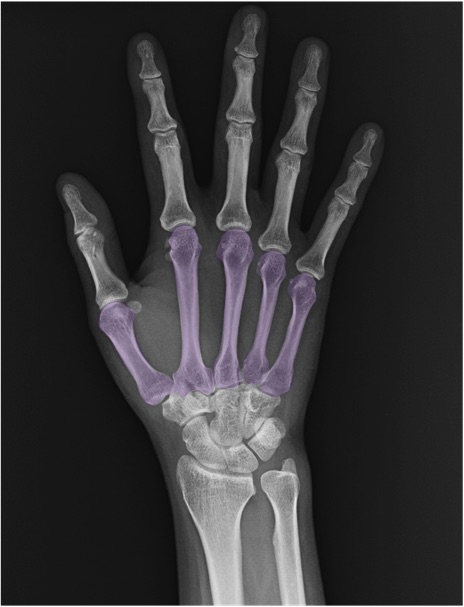

中手骨(metacarpal bone)の手関節レントゲン画像における正常解剖

症例